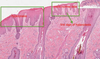

Morphologic diagnosis (MDx)

based on the predominant lesion(s) in the tissue(s); macroscopic, microscopic; summary of the lesion, but generally does not describe what is causing the lesion

- location (organ tissue)

- distribution (focal, multifocal, locally extensive, diffuse)

- severity (mild, moderate, severe)

- duration/time (acute, chronic)

- nature (degenerative, inflammatory, neoplastic) of the lesion; if inflammatory remember to classify the type of exudate

(ex. [small intestine], segmental necrohemorrhagic enteritis)